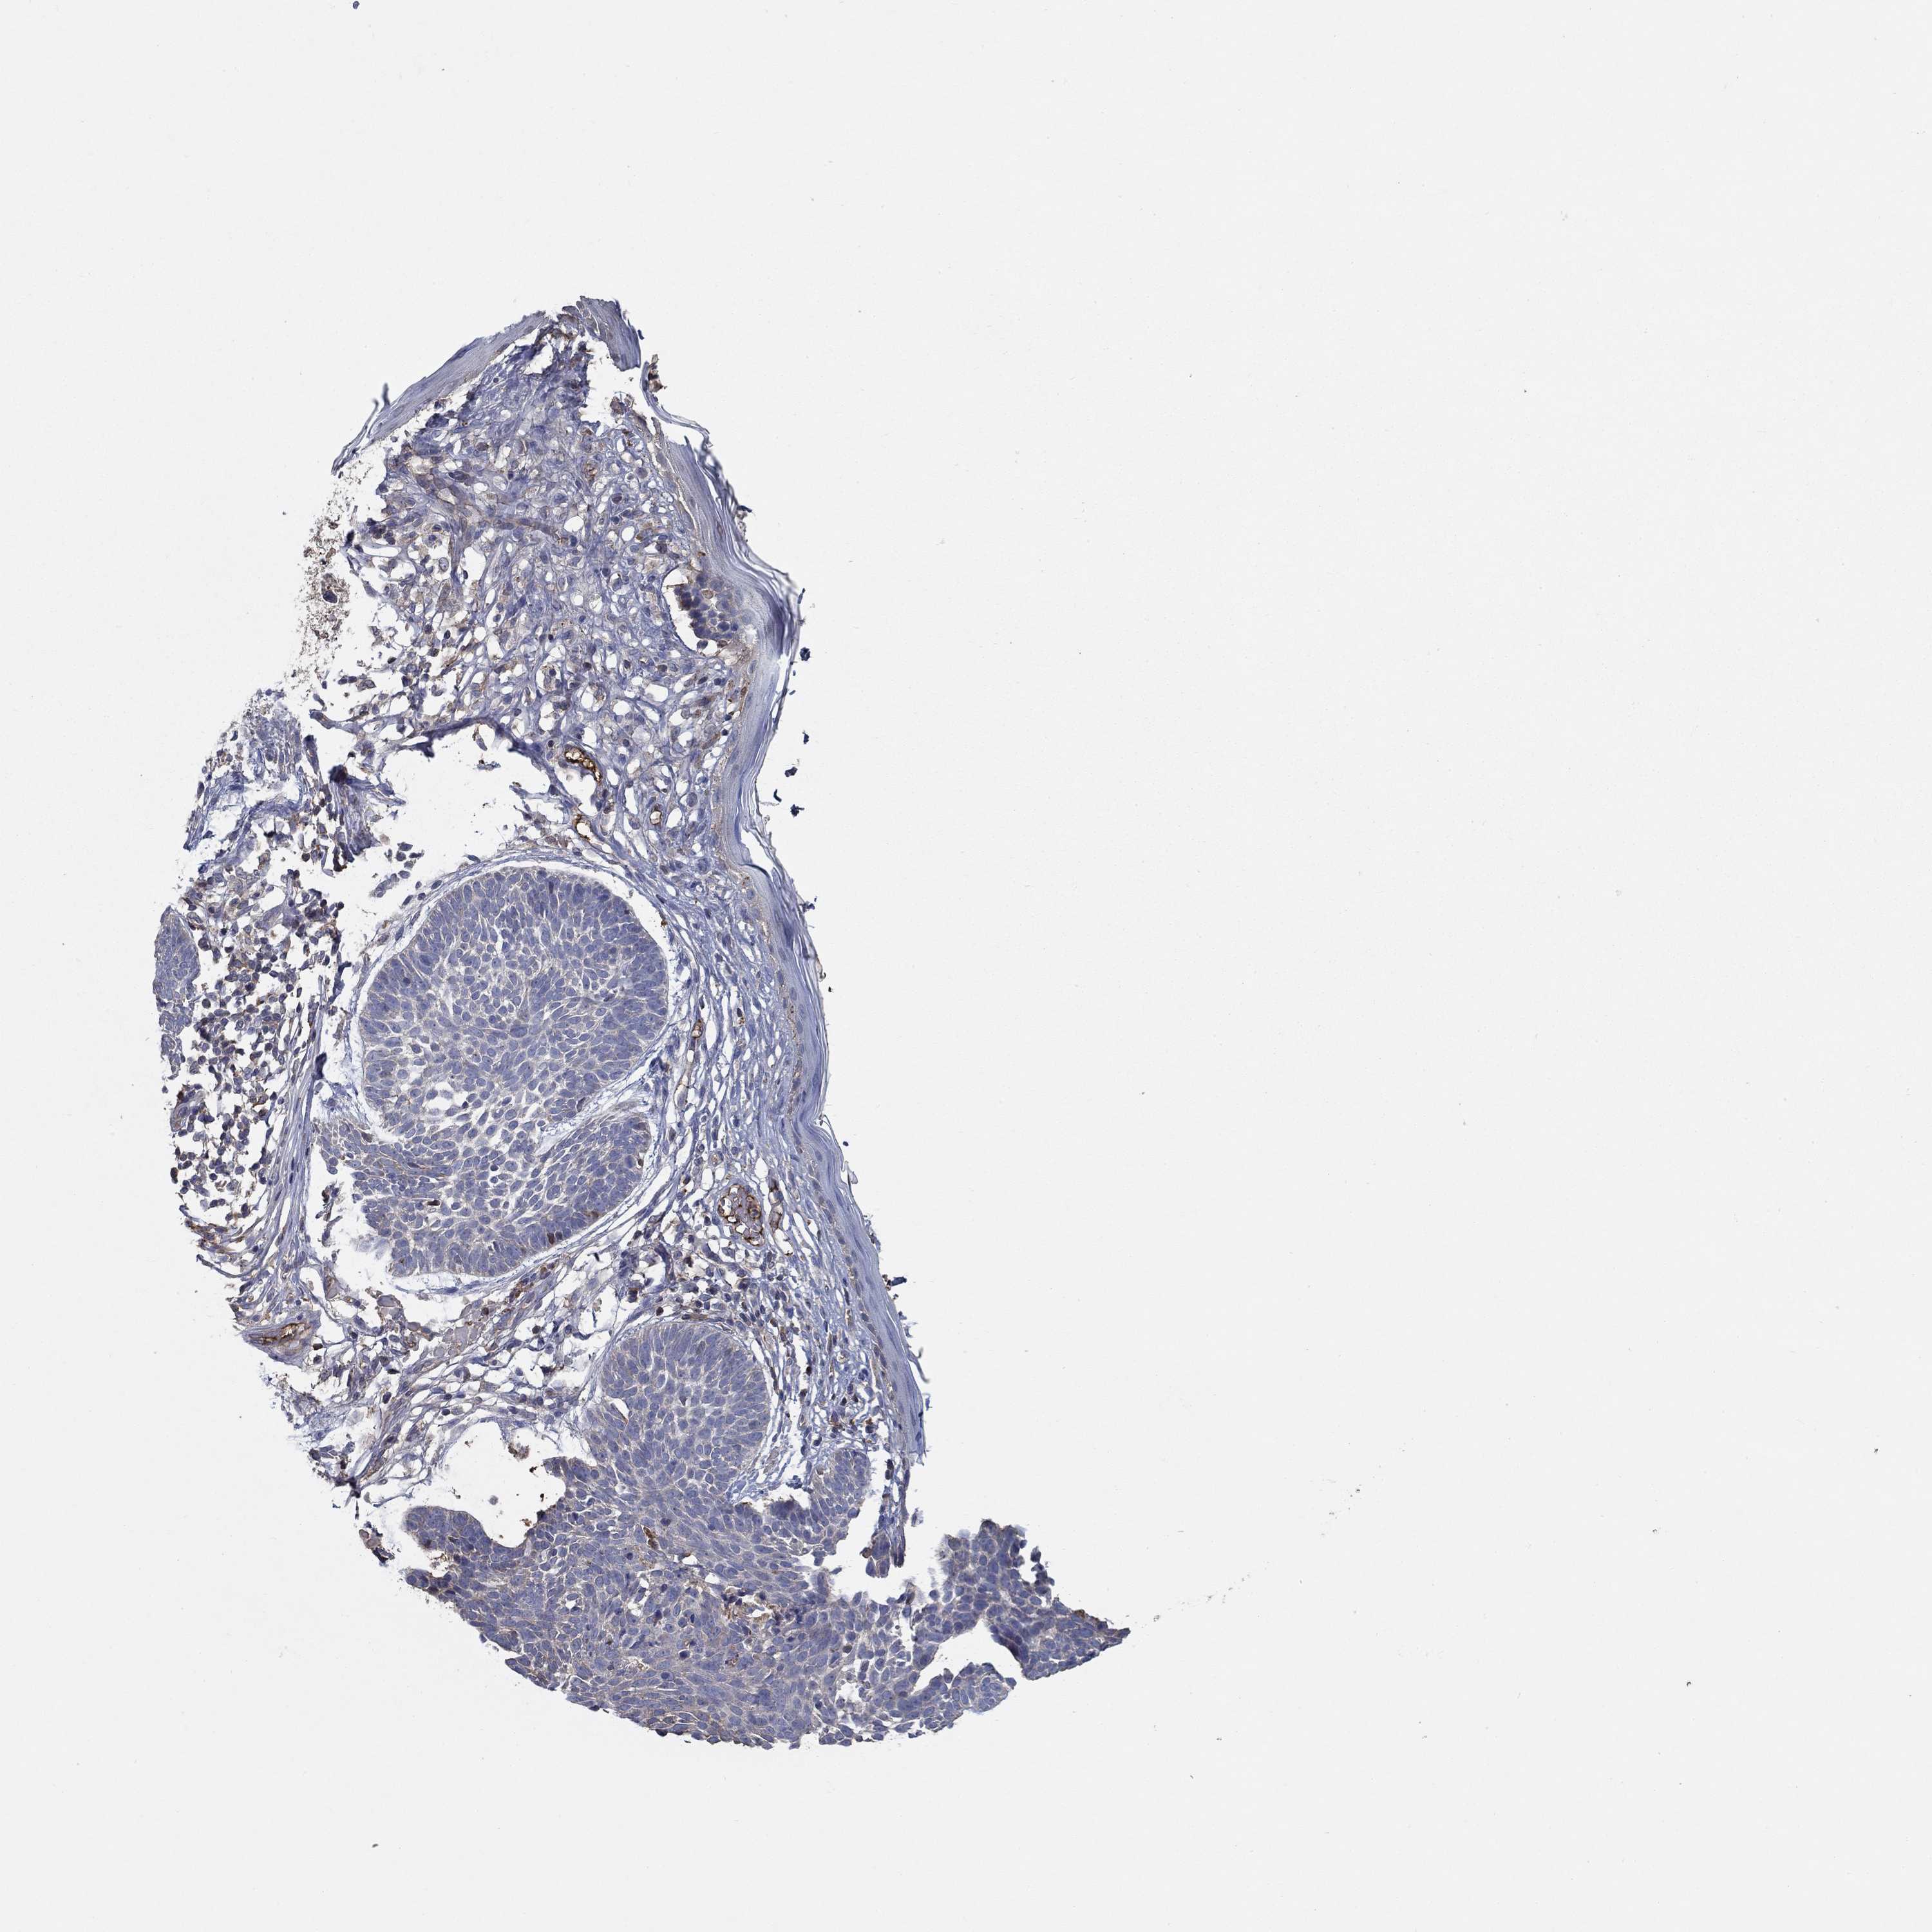

SKIN CANCER - Protein expressioni

A mouse-over function shows sample information and annotation data. Click on an image to view it in a full screen mode. Samples can be filtered based on level of antibody staining by selecting one or several of the following categories: high, medium, low and not detected. The assay and annotation is described here.

Antibody stainingi

Antibody staining in the annotated cell types in the current human tissue is reported as not detected, low, medium, or high, based on conventional immunohistochemistry profiling in selected tissues. This score is based on the combination of the staining intensity and fraction of stained cells.

Each image is clickable and will lead to virtual microscopy that enables deeper exploration of all samples and also displays staining intensity scores, fraction scores and subcellular localization as well as patient and tissue information for each sample.

Antibody HPA071391

Antibody CAB013120

Basal cell carcinoma

Squamous cell carcinoma, NOS